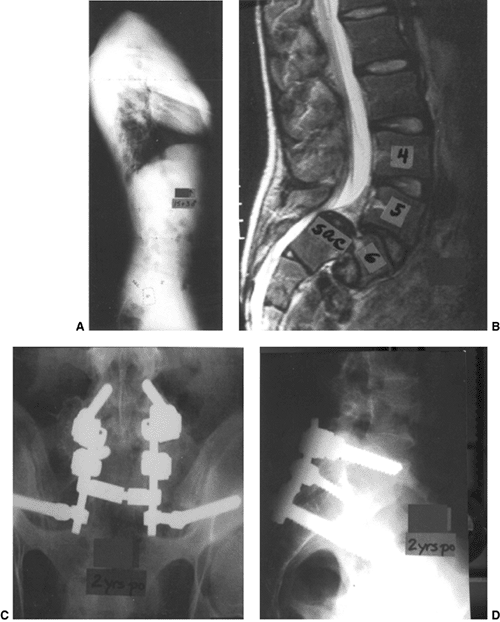

Figure 21.13 A and B:

This patient, a girl 11 years and 8 months old, had 50% back pain and 50% leg pain from a low-grade L-5 spondylolisthesis. Following failure of conservative treatment, she underwent a posterior decompression and instrumented posterolateral fusion from L-5 to the sacrum with autogenous iliac crest graft laterally. C: At 5 years 6 months postoperatively, she had an excellent solid arthrodesis seen on this Ferguson posteroanterior view. D: The lateral view, showing a stable L-5–S1. |